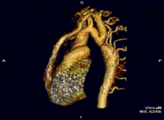

Sindomul Marfan si alte afectiuni

asociate ce implica aorta

Dintre afectiunile majore mostenite ce afecteaza inima

si aorta in timpul nasterii sindromul Marfan (cu o

incidenta in populatia generala de 1/5000) este cel mai

important in lume. Unusprezece tipuri de sindrom

Ehlers-Danlos au fost definite, cu o incidenta sumata

de 1/5000 nasteri. Atingerea aortica apare primar in

sindromul Ehlers-Danlos tip IV. Alte forme familiale

de anevrism si disectie de aorta toracica pun de

asemenea probleme de management in timpul sarcinii.

Sindromul Marfan

Sindromul Marfan este cea mai grava, mostenita

autosomal dominant, deficienta a fibinei-1, afectand

toate sistemele, dar mai ales ochii, inima si scheletul.

Semne clasice de afectare a 2 din 3 sisteme principale

constituie criteriul de diagnostic. La 25% din pacienti

sindromul apare prin mutatie spontana, dar 75% au

antecedente heredo – colaterale pozitive.

Antecedentele privind evolutia in timpul sarcinii a

femeilor afectate si, daca este disponibil, diametrul

radacinii aortei la momentul disectiei sau operatiei

sunt de ajutor in decizia asupra unui plan de

management medical. Varsta la care anevrismul aortic

a aparut la alte femei ne orienteaza, dar este o mare

variabilitate chiar si in cadrul aceleiasi familii.

Anevrismul, ruptura si disectia aortei ramin

inca cele mai frecvente cauze de deces in sindromul

Marfan. Sarcina este o perioada cu risc crescut pentru

femeile afectate, la care disectia apare cel mai frecvent

in ultimul trimestrul sau precoce in postpartum.

Evaluarea completa e necesara inainte de sarcina si

implica examinare ecografica a inimii si a intregii

aorte. Femeile cu afectare cardiaca minima ( diametrul

radacinii aortei sub 4 cm si fara regurgitare aortica sau

mitrala semnificativa ) vor fi informate asupra unui

risc de 1% de disectie de aorta sau de alte complicatii

majore ca endocardita infectioasa sau insuficienta

cardiaca congestiva, pe parcursul sarcinii. Pacientelor

cu un diametru al radacinii aortice mai mare de 4cm li

se va explica ca au un risc de disectie aortica de 10%

pe parcursul sarcinii. Argumentele pro si contra